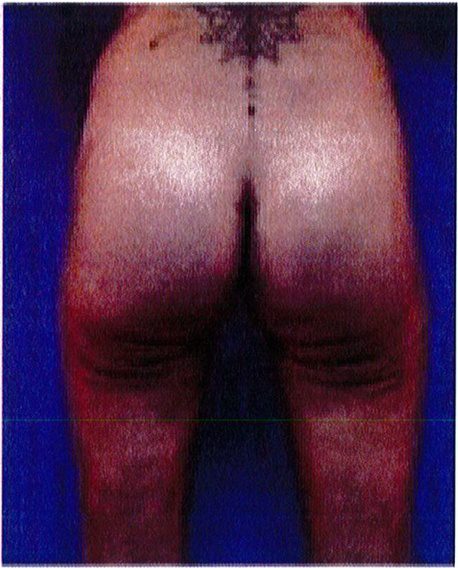

Hình. 18.. (A) Hình anh trước và (B) và sau phẫu thuật làm đầy mông của bệnh nhân được đặt khối implant dưới cân thể tích 225 mL, hai bên.

Bệnh nhân 31 tuổi tiền sử khỏe mạnh, có chỉ định nâng mông bằng implant do thiếu hụt thể tích. Hai khối anatomic implant 225 mL polyurethane dạng gel được đặt ở vị trí dưới cân. Sau phẫu thuật không ghi nhận biến chứng trong suốt quá trình hồi phục, vết mổ liền tốt (Hình 18).